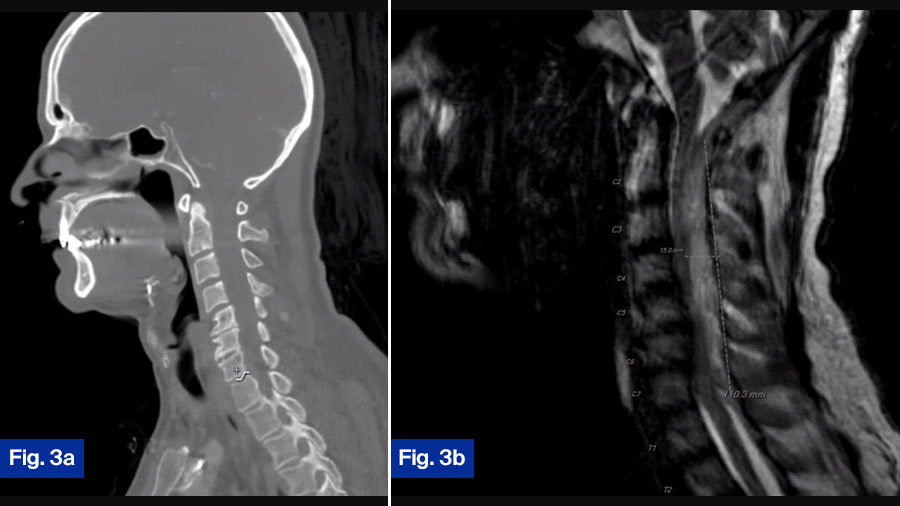

- CT scan: Showed minimal bony destruction (Figure 3a).

- MRI scan: Demonstrated a large dorsal epidural fluid collection spanning C2-T1 with substantial spinal cord compression (Figure 3b).

This patient has a large dorsal collection that is causing severe spinal cord compression and a neurological defect. This patient needs to go to the operating room emergently for a posterior cervical decompression and fusion. While there may, I think, be reasonable arguments for and against early surgical intervention in most patients with a spinal infection, I do not think there is any debate about patients with an acute neurologic deficit. All of these patients should go emergently to the OR.

Charlotte Dandurand: